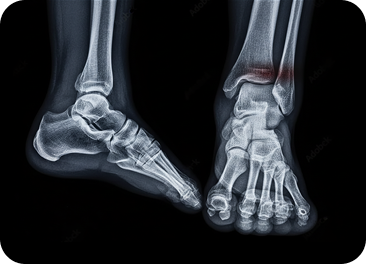

Conditions Affecting Ankle Stability & Motion

We assess traumatic injuries, overuse syndromes, cartilage damage, and chronic instability affecting ankle function, with emphasis on joint integrity and controlled mobility.

Ankle Fractures

Breaks involving the tibia, fibula, or talus requiring alignment assessment andstability evaluation.